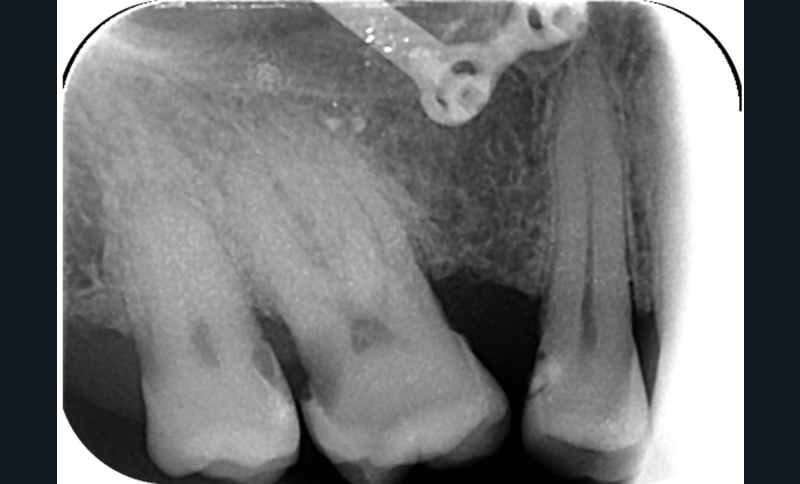

La version des dents distales peut aussi avoir des conséquences parodontales désastreuses : sur un parodonte réduit, une hypermobilité peut se développer, une poche parodontale peut aussi apparaître. Chez un patient parodontal, un « effet domino » est possible, des extractions non compensées diminueront donc le pronostic des dents restantes (fig. 7 à 9).